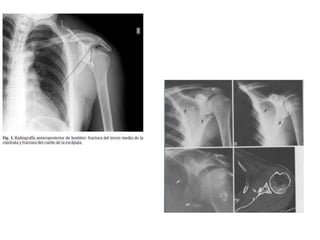

Fracturas de escápula:

Antero-posterior y lateral para cuerpo y acromion;

proyección Stryker para practuras de la apófisis

coracoides.

TAC con reconstrucción 3D en plano transversal.

Si hay neumo o hemotórax asociado agregar radiografía

simple de tórax.